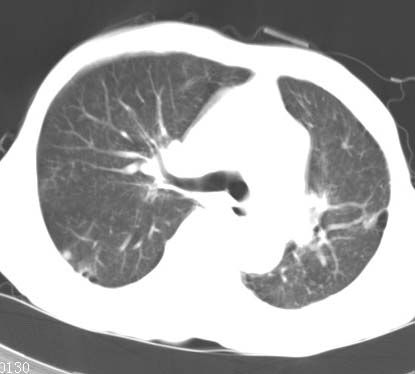

标题: CT14816:男性81岁 胸痛 咳嗽2月 2周前提示右下肺感染. [打印本页]

标题: CT14816:男性81岁 胸痛 咳嗽2月 2周前提示右下肺感染.

男性病人 81岁 胸痛 咳嗽2月 2周前提示右下肺感染.

今片ct示双肺多发结节影 可以这样诊断吗?1\双肺感染性病变 结核待排.

2\双肺纤维硬结灶,左肺肺气肿.

3\肺间质纤维化,胸膜肥厚粘连.

纵隔左移双肺上叶纤维硬结,肺气肿,双侧斑痕肺大泡,双侧胸膜增厚并胸膜下陈旧性病灶,右肺下叶胸膜下小结节影,密度较淡,建议复查.

病人桶状胸,胸廓肌肉消瘦;两上肺均可见纤维条索灶,下肺外围胸膜下可见间质纤维化改变,右下肺沿肺纹理分部结节样病灶,边缘光滑,考虑1、慢支并局灶性间质纤维化、右下肺合并感染,2、两上肺为陈旧性肺结核灶并瘢痕旁型肺气肿3、右下肺转移瘤待排。

两肺上叶见多发索条状高密度影,右肺下叶见片状、结节状高密度影,两肺体积增大,胸膜下区见囊状低密度影、内有分隔结构。左肺下叶见网格影。两侧胸膜见增厚影。诊断:两肺继发性肺结核。慢性支气管炎合并感染。肺气肿。肺间质纤维化。胸膜增厚。